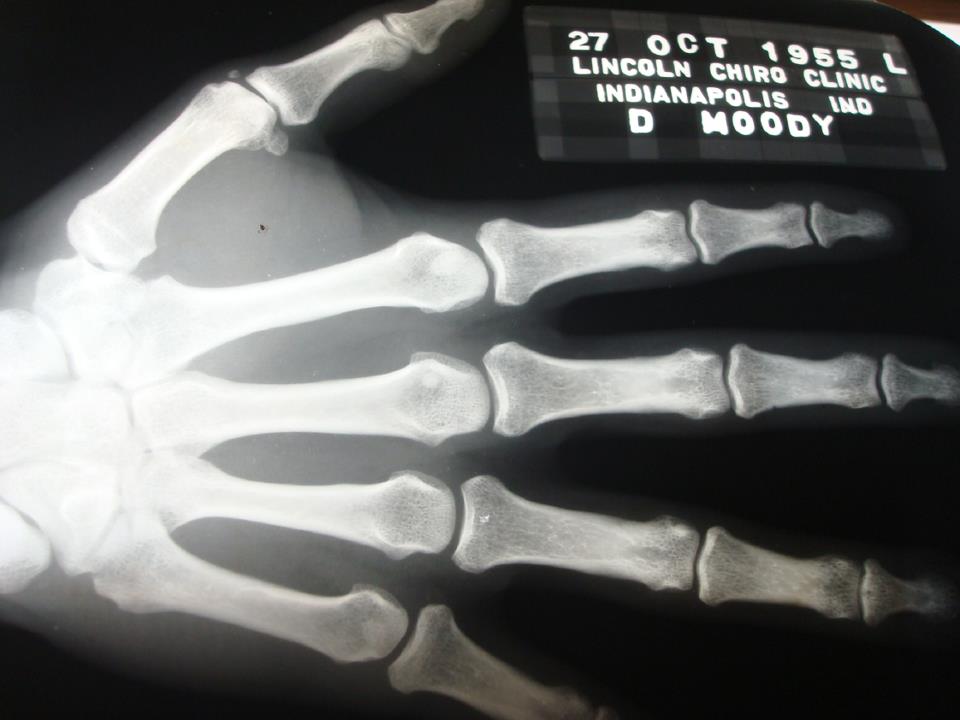

I looked through his books and found a copy of Spear’s Painless System and a unique Lincoln Chiropractic School workbook on X-rays with a few films inside — some were of him even! Perhaps this “personal connection” thing was a little too revealing.

I did a quick walk through the house looking for anything else that belonged in this chiropractic treasure run. I was hoping to find a class composite, as it would have completed this ensemble nicely. Despite turning the house upside-down, I didn’t find one. However, my snooping around paid off, as I found some framed diplomas that were hidden away in a dark corner. Here is a photo of his x-ray certification from Lincoln, year 1957. Notice how it refers to Spinography.